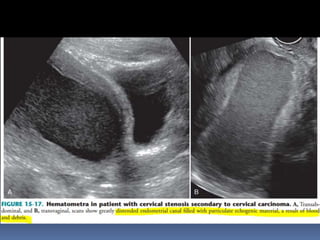

This document contains an image gallery from Dr. Mohit Goel showing various uterine anomalies and ovarian cysts. It includes images of an arcuate and unicornuate uterus, endometritis, a twisted ovarian pedicle, dermoid cysts of varying sizes and echogenicity containing hair, fat, and calcifications, and a combination dermoid cyst showing both mesh and plug structures. The gallery provides ultrasound images of different gynecological conditions for medical education and reference.